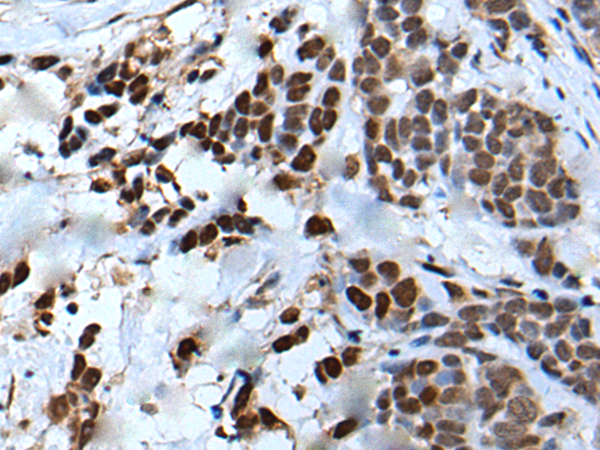

分类: 科研抗体货号: P12878别名: OOMD5; WEE1B应用: IHC反应种属: Human